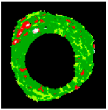

Figure 2 illustrates the result of thresholding, edge detection, region growing [65], level set [66], and active contour (sank), and Figure 3 illustrates the results of clustering using the K-means algorithm.

Figure 3.

Clustering by K-means, (a) cluster 1, (b) cluster 2, (c) cluster 3, and (d) cluster 4.

As illustrated in Figure 2 and Figure 3, unsatisfactory segmentation results are obtained in terms of the overlap borders in the VH-IVUS image, so an accurate algorithm should be developed.